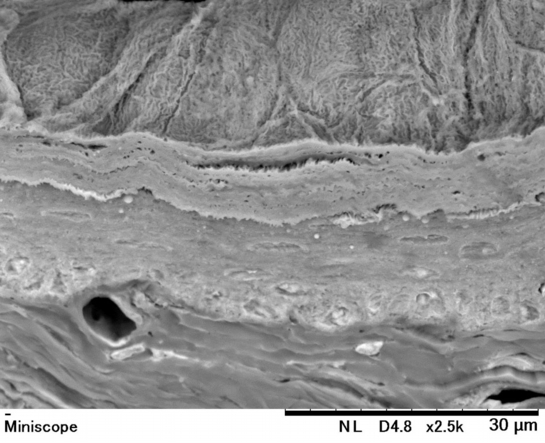

食 道(ラット) Esophagus ( rat )

【 厚さ30 µm パラフィン切片の低真空走査型電子顕微鏡画像 】

Low-voltage scanning electron microscopic image of 30 µm-thick paraffin section